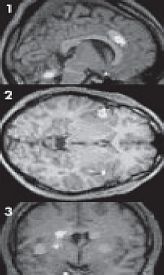

Одной из самых активных зон головного мозга, при влюбленности, является подкорковая зона (1 – боковой срез, яркие пятна). Если посмотреть на снимок после, сканирования, можно наблюдать зоны, которые активны в период влюбленности. Это те же участки удовольствия (области "радости"), что свойственны человеку, употребляющему наркотики. Подкорковая зона головного мозга (одна из самых древних), отвечающая за базовые потребности человека, такие как: пища, утоление жажды, кислород, отдых и даже за то, чтобы организм не перенагревался! В период влюбленности, эта область работает очень интенсивно. Равно, как и активны в момент влюбленности височные отделы (2 – вид сверху) и гипофиз (3 – вид сзади). Представьте себе тот трагический момент, если мы перестанем в этом нуждаться и удовлетворять естественную, биологическую потребность? Тогда, нас ждет только одно, смерть (медленное угасание). И ведь любовь не менее важный процесс нашей деятельности, чем утоление чувства голода и жажды воды!